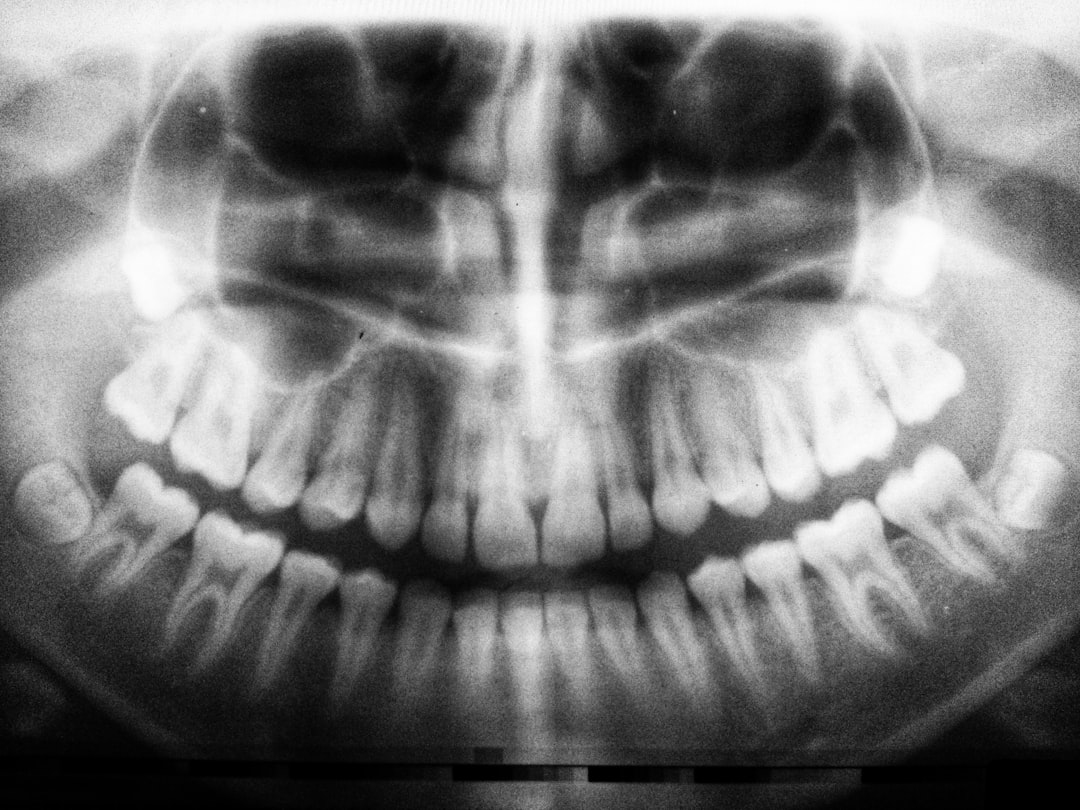

Imagerie diagnostique

L’imagerie constitue l’outil diagnostique de référence :

- Radiographie panoramique : examen de première intention, visualisant les lésions radio-claires

- Scanner cone beam (CBCT) : analyse tridimensionnelle précise des rapports anatomiques

- IRM : caractérisation du contenu kystique et des tissus mous adjacents

Le CBCT s’impose comme l’examen de choix pour la planification chirurgicale, permettant une évaluation précise des risques anatomiques.